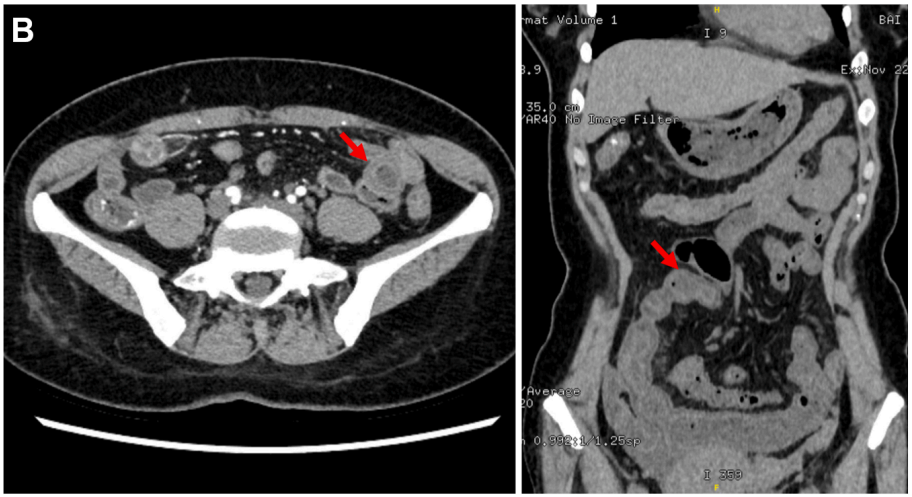

病史摘要:患者为 49 岁女性,因“反复胃肠道息肉切除 17 年余,腹胀 3 天”入院。既往有多部位囊肿,曾行右侧颈部神经鞘瘤手术。家族中父亲、两个哥哥均有结肠息肉相关病史。2008 年首次发现胃底、胃体、结肠等多发性息肉,病理为胃底腺瘤性息肉,此后多次行胃肠镜检查及内镜下息肉切除术。 诊疗过程:入院查体生命体征平稳,慢性病容,上腹轻压痛。2019 年基因检测提示 A